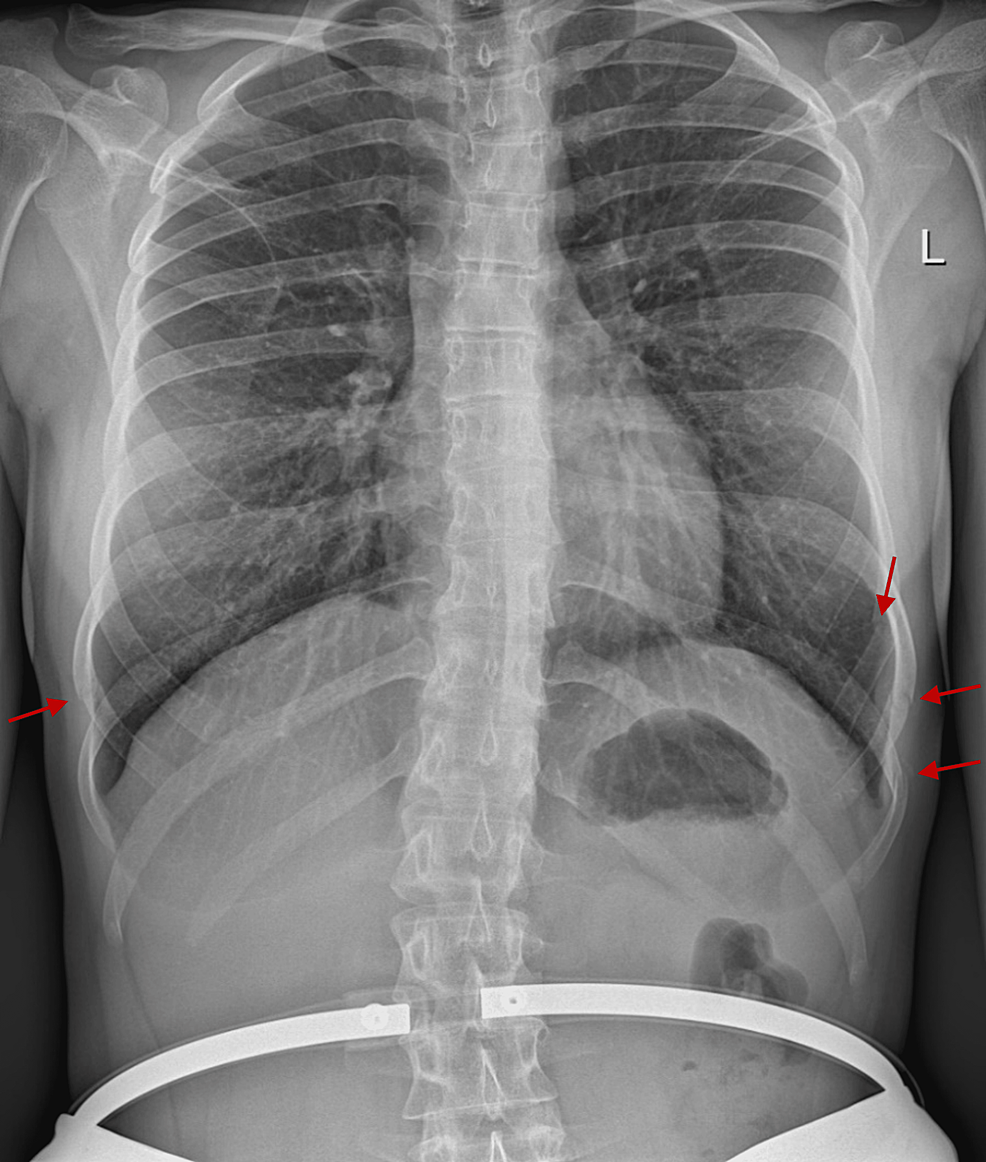

From www.cureus.com

Cureus Clinical and Radiological Aspects of Coughinduced Rib Rib Fracture With Coughing Multiple fractures were more commonly seen in older patients. Rib fractures are common injuries that occur most often following blunt thoracic trauma but can also result from severe. Rib fractures can be very painful. A cracked rib is a type of rib fracture that can occur with a fall, car accident, sports injury, or violent coughing. Middle ribs along the. Rib Fracture With Coughing.

Rib Fragility Fractures and Chest Wall Hematoma After Cardiopulmonary Rib Fracture With Coughing Breathing risks from rib fracture. The central symptom is pain when you inhale. Rib fractures can be very painful. The pain is usually worse with movement, coughing, and deep breathing. When patients sustain a rib fracture, pain may preclude normal breathing or secretion clearing. Multiple fractures were more commonly seen in older patients. A cracked rib is a type of. Rib Fracture With Coughing.